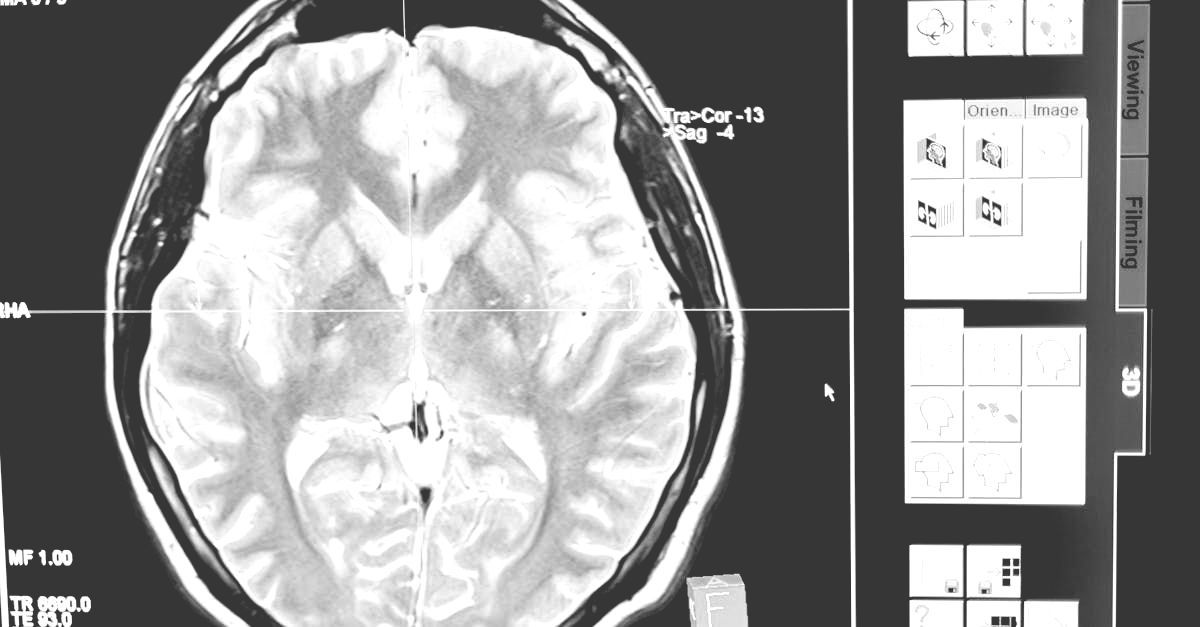

In August 2020, Thriftmaster partnered with Augusta University and Dr. Babak Baban to explore the therapeutic potential of our proprietary CBD blend and Metered Dose Inhaler delivery system. TGB provides the university funding, product formulation and research support, resulting in exclusive rights to the intellectual property created by Dr. Baban's research. This collaboration has led to the publication of six peer-reviewed papers focused on TGB’s inhaled CBD blend and delivery system as a therapy for severe conditions. Many additional studies are in progress. Dr. Baban is preparing to initiate human clinical trials for these conditions (Glioblastoma and Alzheimer's therapy) pending FDA approval.

TGB actively broadens our pre-clinical testing initiatives to assess the therapeutic potential of our products across a diverse spectrum of conditions, with primary focus on the brain, lungs and central nervous/inflammatory system(s). Our unwavering commitment to rigorous research positions us at the forefront of innovative therapies in this theater of study.